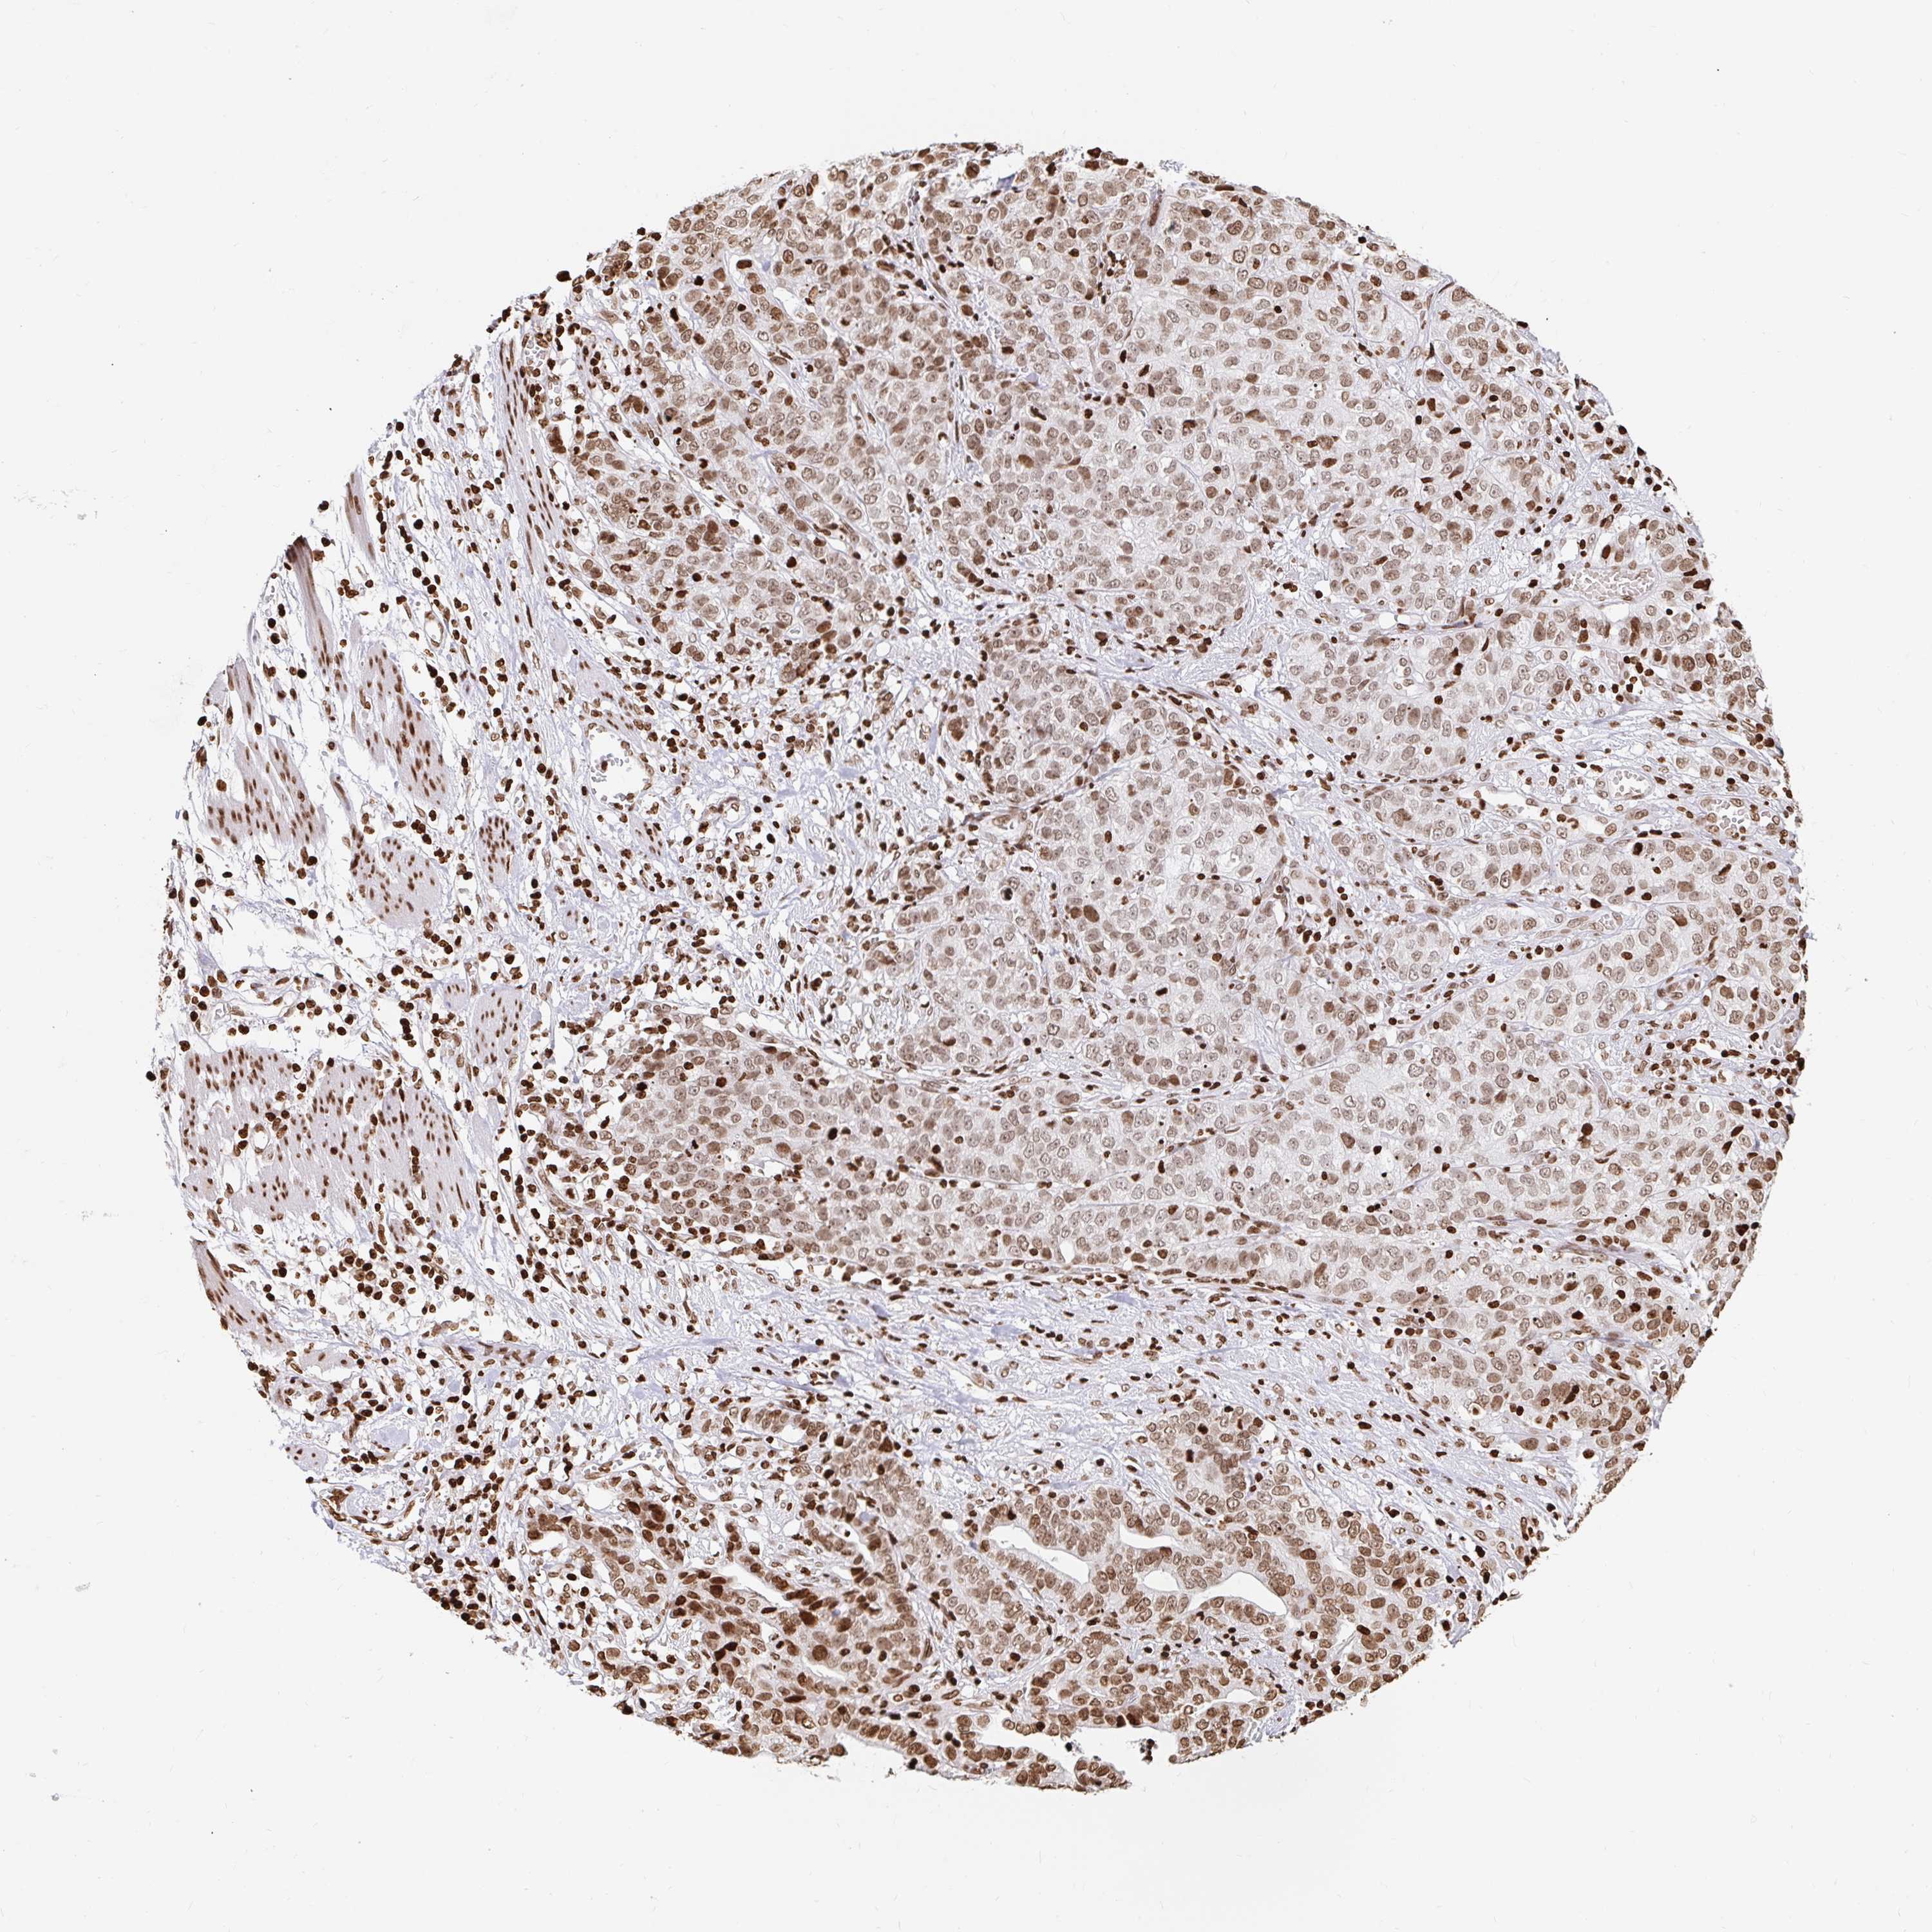

STOMACH CANCER - Protein expressioni

A mouse-over function shows sample information and annotation data. Click on an image to view it in a full screen mode. Samples can be filtered based on level of antibody staining by selecting one or several of the following categories: high, medium, low and not detected. The assay and annotation is described here.

Note that samples used for immunohistochemistry by the Human Protein Atlas do not correspond to samples in the TCGA dataset.

Antibody stainingi

Antibody staining in the annotated cell types in the current human tissue is reported as not detected, low, medium, or high, based on conventional immunohistochemistry profiling in selected tissues. This score is based on the combination of the staining intensity and fraction of stained cells.

Each image is clickable and will lead to virtual microscopy that enables deeper exploration of all samples and also displays staining intensity scores, fraction scores and subcellular localization as well as patient and tissue information for each sample.

Antibody HPA042205

Antibody HPA043013

Antibody HPA048671

Antibody CAB062336

Staining

High

Medium

Low

Not detected

Intensity

Strong

Moderate

Weak

Negative

Quantity

>75%

75%-25%

<25%

None

Location

Nuclear

Cytoplasmic/membranous

Cytoplasmic/membranous,nuclear

Adenocarcinoma, NOS